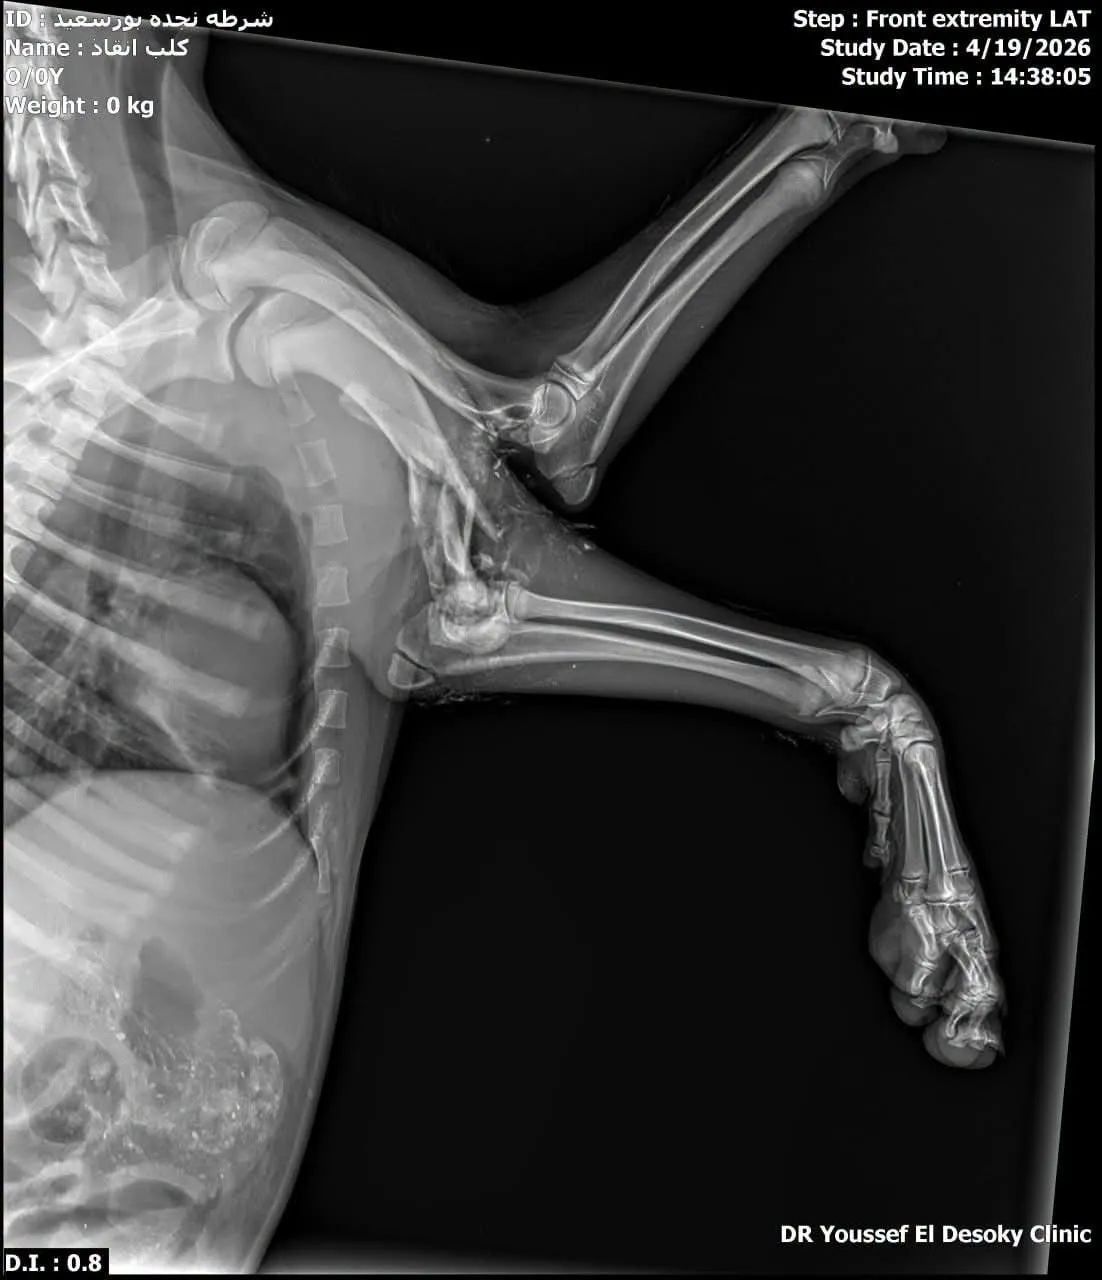

وأشار في تصريح خاص لـ "اليوم السابع"، إلى أن الكلب أصيب بكسر وجرح قطعى، ويتم التعامل السريع معه، بغرفة عمليات الشلتر وبعدها سيتم رعايته حتى تتحسن حالته الصحية.

واستقبل الدكتور محمد عيسى مدير المستشفى البيطري والمسؤول الطبي عن شلتر بورسعيد، حالة الكلب لاستكمال العلاج داخل الشلتر، بعد وصول السيارة الخاصة بها لنقل الكلب المصاب إلى شلتر بورسعيد.